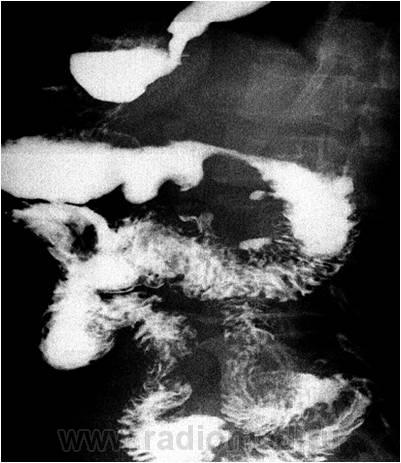

4. Спайки кишечника ведут к стойкой деформации кишки, изменению обычного положения ее петель, ограничению пассивной и активной подвижности и сужению просвета различной степени, иногда с супрастенотическим расширением кишки, метеоризмом и нарушением пассажа бариевой взвеси. Контуры суженного участка четкие, неровные, зазубренные, с характерными остроконечными выступами, меняющими свою форму и размеры в процессе исследования, особенно при дозированной компрессии или раздувании газом (1-й случай).

5. Вызванные сращениями резкие перегибы и сужения кишки обусловливают соответствующую рентгенологическую картину. При спаянии между собой соприкасающихся соседних петель может образоваться нерасправляющаяся во время исследования так называемая «двустволка». (2-й случай) Характер подобной деформации лучше определяется в условиях двойного контрастирования кишки. При этом изучают состояние рельефа слизистой оболочки и. эластичности стенок, особенно в зоне деформации и перегибов кишки. Складки слизистой оболочки в подобных случаях хотя и деформируются, перекручиваются и меняют обычное направление или сглаживаются, однако в отличие от опухолевого процесса прослеживаются на всем протяжении, не обрываясь. О спаечном процессе говорит также отсутствие ригидности стенки кишки, что свойственно злокачественной опухоли.

2.Выявлении при полипозиционном исследовании различного вида деформаций, (1-й представленый случай - угловая деформация, как ведущее проявление процесса) необычной фиксации, изменений положения и контуров, сращений с брюшной стенкой или соседними органами вовлеченного в процесс органа (органов) (3-й случай).